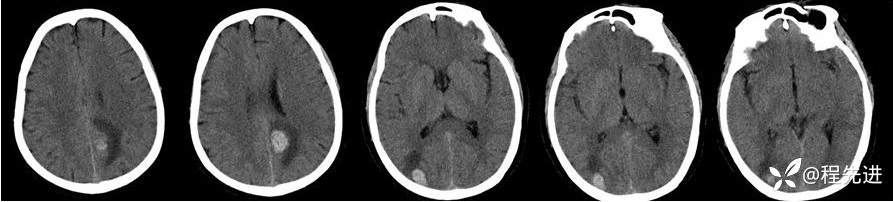

CT:

img